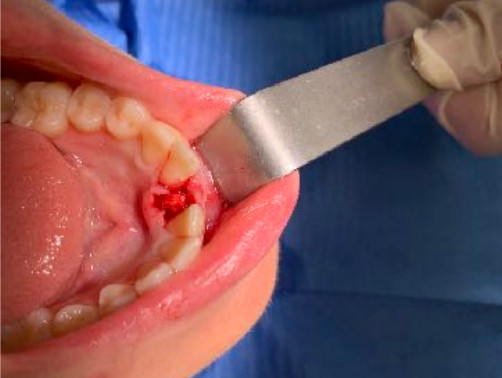

The reduced diameter of the neck allows you to protect yourself from any peri-implantitis and significantly improves the speed of healing. In this case it was tapped with a diameter of 4 and a Tramonte implant with a diameter of 4 mm with 7 threads with short neck was inserted. The titanium used is always grade 4.

| Extractive situation: Immediate post-extraction implant with immediate loading. | Density according to Misch: D2 |

| Drill sequence: Lanceolate cutter only | Sequence of taps: tap diameter 4 mm |